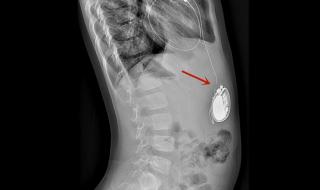

全磁浮心脏即离心泵人工心脏,被称为第三代人工心脏,是目前最先进,对人体影响最小也是最耐用的人工心脏,美国FDA前两年刚上市了第一款,我国高端医疗器械几乎无国产产品。

男子植入最小人工心脏